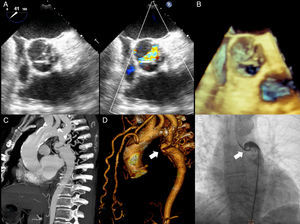

Physical exploration was remarkable for short stature, underdevelopment of lower extremities and laterally displaced apical impulse. Auscultation over the aortic area revealed a harsh meso-telesystolic crescendo-decrescendo murmur IV/VI radiating to carotids and apex with Gallavardin phenomenon. A loud systolic murmur was also heard over the left paravertebral area. Carotid pulse was parvus et tardus. Lower extremities pulses where markedly diminished. Blood pressure was 152/90mmHg in the upper extremities and 64/40mmHg in the lower extremities. Ankle brachial index was 0.42. Chest radiograph showed grade III cardiomegaly, radiographic data compatible with the “3” sign, inferior rib notching (Roesler sign) and calcified collateral vessels (Fig. 1A). The EKG demonstrated a sinus rhythm, complete right bundle branch block, left anterior fascicular block, biventricular hypertrophy and systolic overload of the left ventricle (Fig. 1B). Transthoracic echocardiography showed a calcific severely aortic stenosis with a mean gradient of 44mmHg, peak gradient of 73mmHg and a peak velocity of 4.2m/s. Left ventricular ejection fraction was 49%, there were no regional wall motion abnormalities. Transesophageal echocardiography confirmed a stenosed, functionally bicuspid aortic valve, aortic valve area was 0.6cm2 by planimetry (Fig. 2A and B). CT angiography revealed a markedly diminished descending aorta with a minimum diameter of 4mm measured 35mm after the origin of the left subclavian artery (Fig. 2C and D). Aortic root and ascending aorta size were normal (26 and 36mm respectively).

(A) Posteroanterior chest radiograph demonstrating situs solitus, levocardia, levoapex, left sided aortic arch, normal pulmonary blood flow and grade III cardiomegaly, additionally the “3” sign (red arrow), inferior rib notching (white arrow) and calcified collateral vessels (*). Top left panel delineating the descending aorta contour from the same patient in the thoracic scout CT image. Top right panel is a zoom of the inferior rib notching. (B) Standard 12 lead EKG demonstrating a sinus rhythm, complete right bundle branch block, left anterior fascicular block, biventricular hypertrophy and systolic overload of the left ventricle.

(A) Transesophageal echocardiography aortic short axis view showing a Type 1 bicuspid aortic valve (right–left coronary cusp fusion) with important thickening and color Doppler acceleration. (B) 3D imaging of the aortic valve. (C) Maximum intensity projection CT angiography and (D) volumetric reconstruction showing the severe aortic coarctation site (white arrow) measured 35mm after the origin of the left subclavian artery along with marked collateral circulation (mammary and vertebral arteries). (E) Coarctation site angiography demonstrating the reduction of the luminal area (white arrow) and the anatomic complexity for an endovascular treatment.